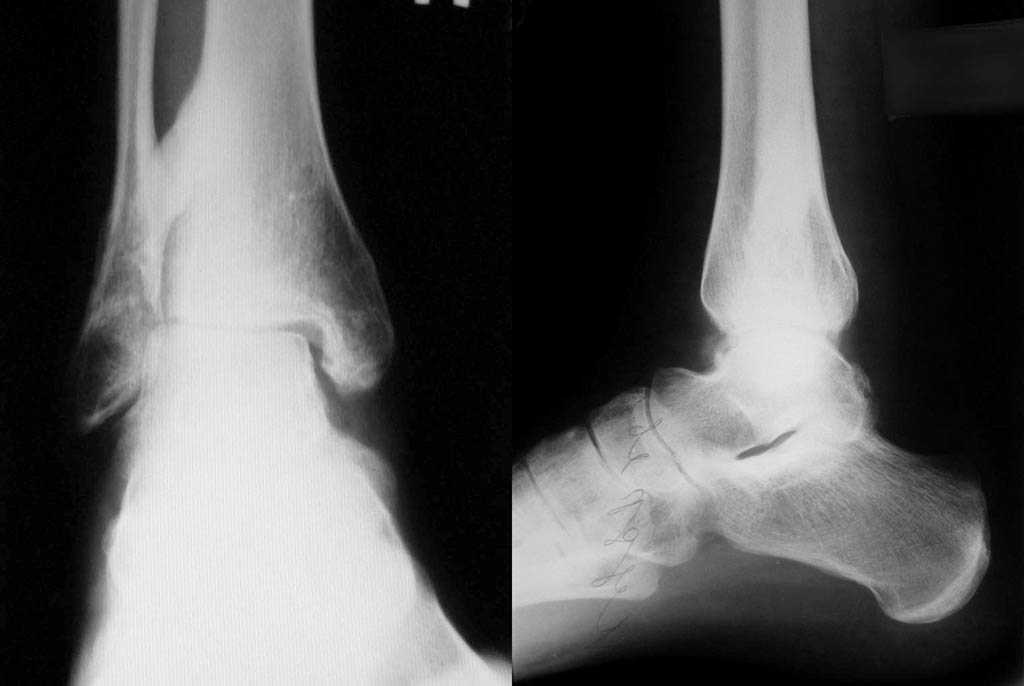

На консультацию обратился пациент 30 лет, вес около 65 кг, с жалобами на боли в голеностопном суставе, недостаток планто и дорсофлексии. Боли беспокоят при нагрузке в области синдесмоза. В анамнезе: в январе 2007г. перелом лодыжек. На Ро снимках 2007 года трехлодыжечный перелом, разрыв дистального межберцового синдесмоза, подвывих стопы кнаружи. Прооперирован в одной из районных клиник. На Ро-контроле после оперативного вмешательства МОС латеральной лодыжки 1-м кортикальным винтом, МОС медиальной лодыжки кортикальным винтом, МОС дистального синдесмоза спонгиозным винтом проведеным четко через зону синдесмоза. В октябре 2007 удаление фиксаторов. На последних снимках дисконгруэнтность суставных поверхностей, гетеротопическая оссификация межкостного пространства у дистального межберцевого синдесмоза и оссификация последнего. Последние снимки прилагаются. Как только появится пациент повторно - планирую выполнить КТ голеностопного сустава на предмет внутрисуставных костно-хрящевых тел. Помогите определиться с дальнейшей тактикой лечения.